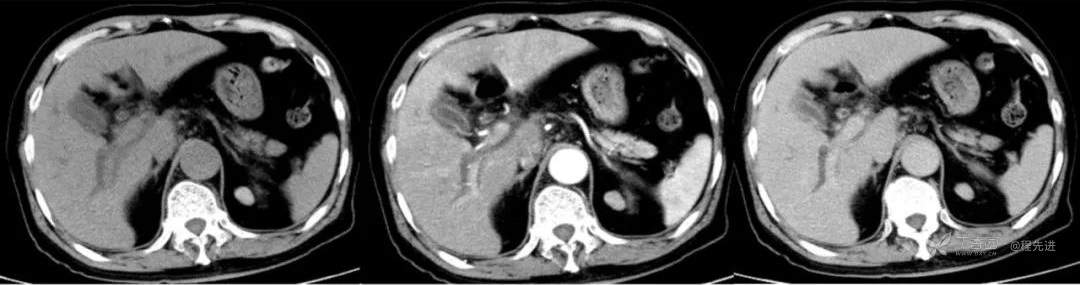

简要病史:因胸部不适入院,胸部CT示:肺部感染性病变;腹部CT示:肝门区占位性病变